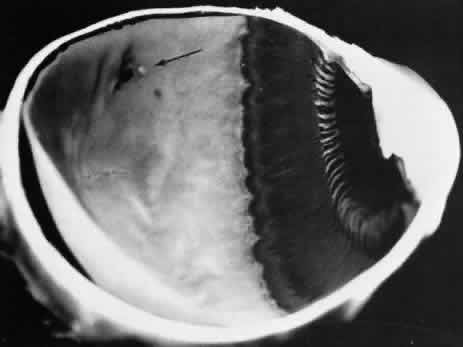

The anterior edge of the peripheral retina is theora serrata, an irregularly scalloped border; the irregularities are more pronounced nasally than temporally and have extreme individual variations in contour (Fig. 5). Dentate or toothlike processes extend anteriorly from the main contour of this bor-der, and bays or indentations extend posteriorly from the main contour of the ora serrata. At theora serrata, those projections of the retina toward the vitreous body are termed meridional folds. There is a concentration of dentate processes, ora bays, and meridional folds in the superior nasal quadrant and a progressive decrease in these morphologic features in the inferior nasal, superior temporal, and inferior temporal quadrants (Figs. 6 and 7). Although individual variations in ora serrata contour may be extreme, studies of adult human eyes demonstrate that both of a patient's eyes are remarkably similar and that statistically, the “average” ora serrata has 16 dentate processes, 1 large or giant dentate process, 10 ora bays, and 1 double ora bay.1,2

Fig. 5. Composite scale drawing depicts peripheral retina, ora serrata, ciliary body, and lens as viewed from posterior aspect. Ora serrata have more dentate processes and ora bays in the nasal quadrants than in the temporal quadrants.

Fig. 6. Peripheral fundus showing preequatorial retina, ora serrata, and inner surface of ciliary body (smooth portion, pars plana; portion with ciliary processes, pars plicata). Ora serrata in this nasal sector shows largely short dentate processes that are typical; that is, they align with valleys between ciliary processes. On right, a giant dentate process is atypical; that is, it aligns with a ciliary process. Aligned with and posterior to the atypical dentate process is a focus of retinal thinning (peripheral retinal excavation). (× 14.)